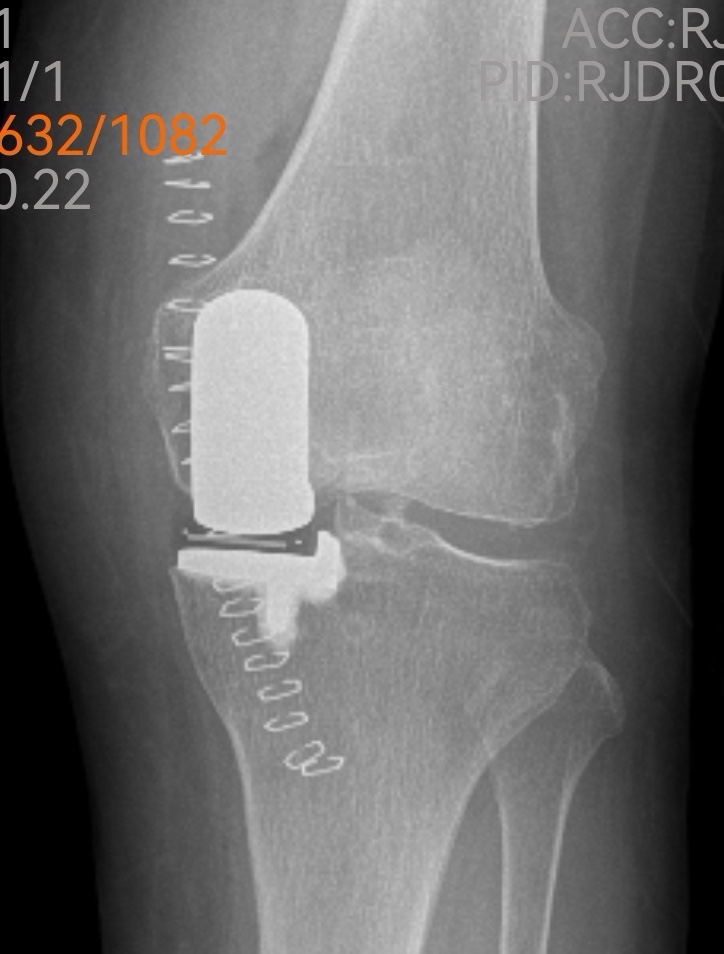

傳統(tǒng)的全膝關(guān)節(jié)置換固然能解決問題,但創(chuàng)傷較大、恢復(fù)期長(zhǎng)。經(jīng)過團(tuán)隊(duì)綜合評(píng)估,魏海清主任提出了一個(gè)更精細(xì)的方案:“我們建議行左膝關(guān)節(jié)單髁置換術(shù)。這就像牙齒壞了,我們不必把所有牙齒都換掉,而是只替換損壞的部分。這種手術(shù)只替換磨損的軟骨和部分骨質(zhì),能最大限度保留健康組織?!彼贸鱿リP(guān)節(jié)模型,耐心地向一家人解釋手術(shù)原理:“您看,膝關(guān)節(jié)分為內(nèi)側(cè)、外側(cè)和髕股三個(gè)部分。您的磨損主要集中在內(nèi)側(cè),所以我們只需置換這一部分。”這種個(gè)體化、精準(zhǔn)化的治療理念,讓原本忐忑的一家人逐漸安心。

微創(chuàng)手術(shù),一小時(shí)改寫生活

手術(shù)室里,骨科、麻醉科、手術(shù)室團(tuán)隊(duì)配合默契。微創(chuàng)切口僅有傳統(tǒng)手術(shù)的一半大小,精細(xì)的操作在關(guān)節(jié)鏡輔助下進(jìn)行。沒有大刀闊斧的創(chuàng)傷,只有精準(zhǔn)細(xì)致的重建。一小時(shí)后,手術(shù)順利結(jié)束,出血量?jī)H約100毫升。“這么快?”等候在外的兒子們幾乎不敢相信。魏海清主任走出手術(shù)室,微笑點(diǎn)頭:“很順利,單髁置換本來就是微創(chuàng)手術(shù),對(duì)患者損傷小?!?/p>